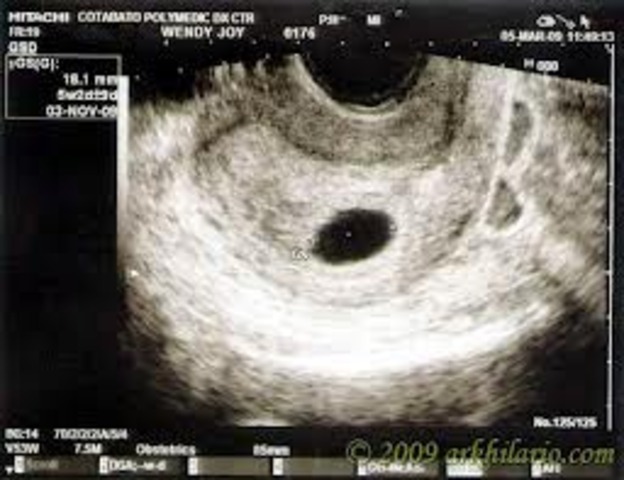

• Month 1

Month 1

Baby ; - Size - at two weeks , the size of a pin head. - Eggs attaches to lining of uterus. -Critical stage for brain and spinal cord development. - Internal organs and crculatory system begin to form. -The heart begins to beat.